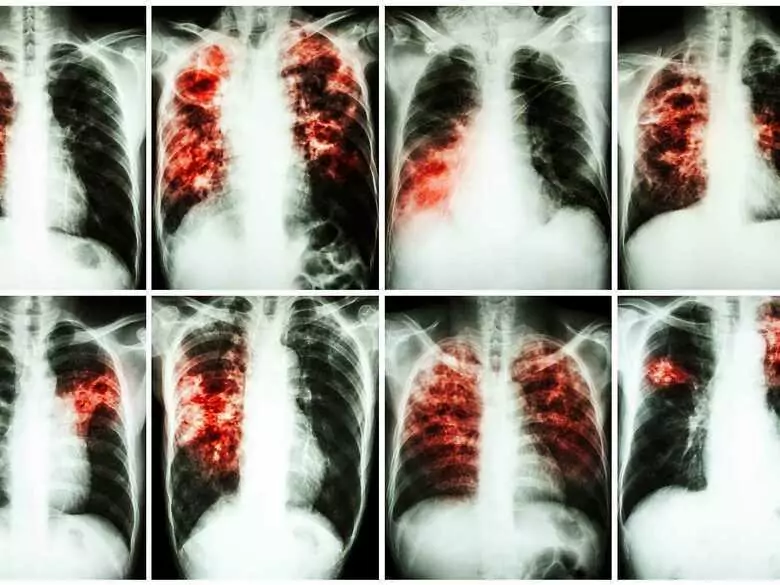

Des chercheurs de la faculté de médecine de Hradec Králové de l'université Charles de Prague ont inventé un nouveau médicament contre la tuberculose. Le médicament a été vendu à une société pharmaceutique américaine, qui développera la spécificité par contrat. L'université de Prague participera toutefois financièrement aux recettes de la vente du médicament.